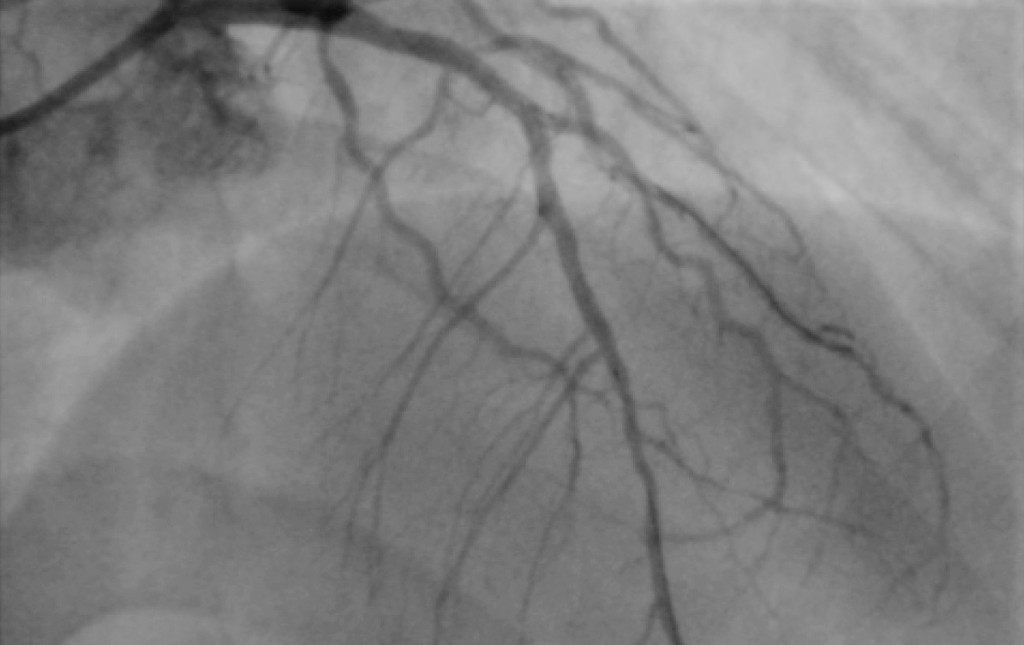

Giuro, questo è il mio cuore. O meglio, ciò che nella tarda serata di San Valentino del 2006 si vide di esso quando aggiunsero un liquido di contrasto nelle coronarie, le famose piccole arterie che portano sangue e nutrimento al cuore stesso in quanto muscolo. Solo poche ore prima, dopo un periodo di mesi di affaticamento per completare un certo progetto in scadenza con poco sonno e tante sigarette, ero in ritardo per vedere un certo programma in televisione, e feci le scale di corsa. Arrivai col fiato corto, ma anche con un qualcosa che mi dava fastidio nel petto, un leggero dolore cupo e persistente, più una pesantezza, come di una cosa non digerita bene. Stavo per fare la conoscenza del signor infarto.